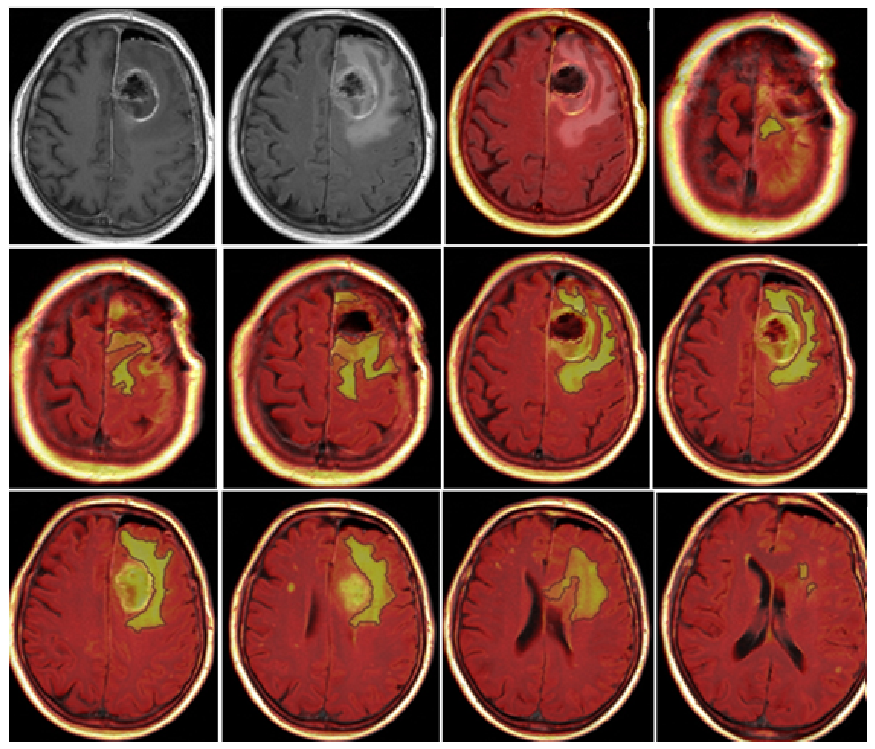

3.2. Quantitative Analysis

- CE-RTV: The median OS value was 19 months for patients with CE-RTV < 5.8 cm3 and 9 months for patients with CE-RTV > 5.8 cm3. The difference was statistically significant (p < 0.004) (Table 2).

- CE-RTV: The median PFS value was 5 months in patients with CE-RTV < 5.8 cm3 and 4 months in patients with CE-RTV > 5.8 cm3. The difference was statistically significant (p = 0.04).